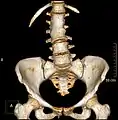

Lumbarization of sacral vertebra 1, seen as 6 vertebrae that do not connect to ribs.

Lumbarization is an anomaly in the spine. It is defined by the nonfusion of the first and second segments of the sacrum. The lumbar spine subsequently appears to have six vertebrae or segments, not five. This sixth lumbar vertebra is known as a transitional vertebra. Conversely the sacrum appears to have only four segments instead of its designated five segments. Lumbosacral transitional vertebrae consist of the process of the last lumbar vertebra fusing with the first sacral segment. [1] While only around 10 percent of adults have a spinal abnormality due to genetics, a sixth lumbar vertebra is one of the more common abnormalities. [2]